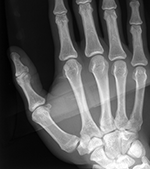

Which examinations may be considered in an individual case depends on the procedural situation and the legal basis. Typical components are the physical examination, the dental examination including orthopantomogram, the radiological assessment of the hand, and, in cases of advanced maturity and a corresponding question, supplementary findings at the clavicle. What is decisive is the ordered overall appraisal; an isolated single finding does not carry the conclusion. The evidential value therefore does not arise from a single image or a single maturity feature, but from the methodologically grounded combination of the permissible findings.